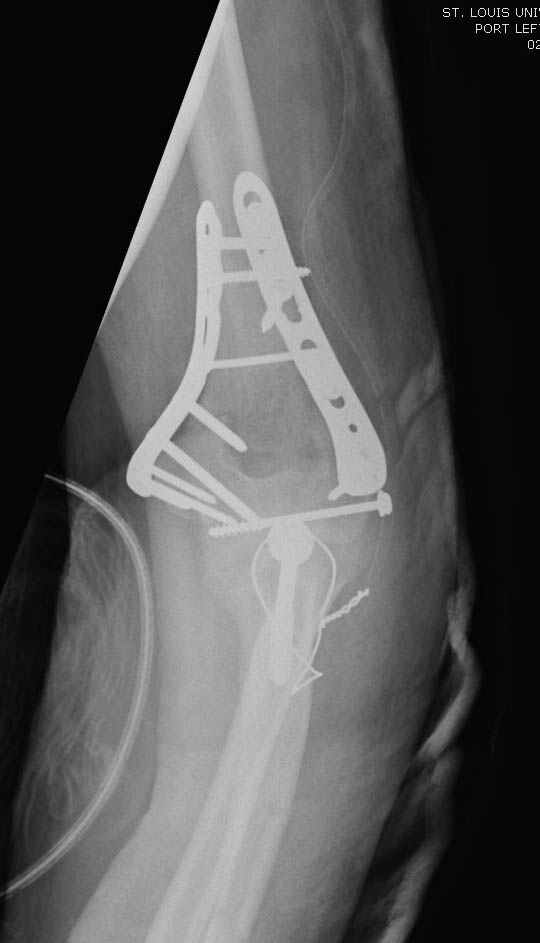

На шестой день сделали открытую репозицию чрезлоктевым доступом двумя locking plate, локтевой нерв был ушибленным, после операции положительная динамика в Flexor Carpi Ulnaris. Фиксацию локтевого отростка произвели tension band technique с дополнительным шурупом.

Этапы операции на снимках....